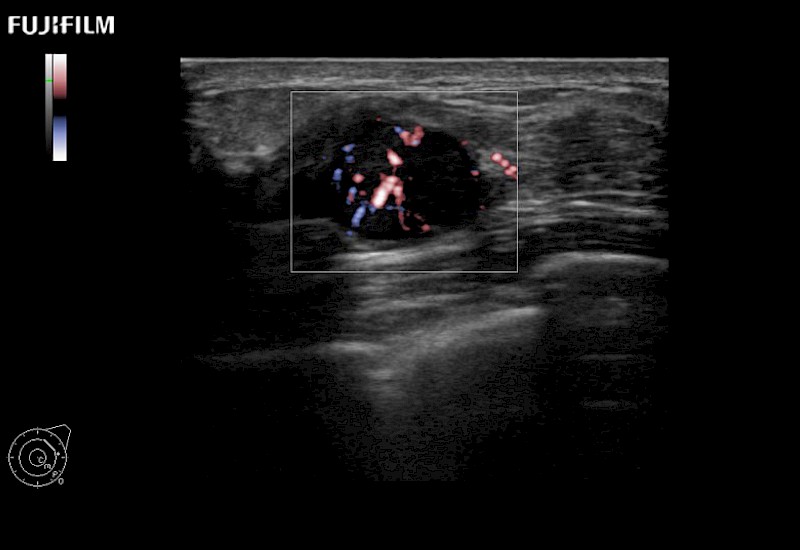

The ARIETTA 650 DI combines trusted Fujifilm Healthcare technologies and features tailored for surgical oncology.

Designed to meet the demands of surgeons, the ARIETTA 650 DI offers precise guidance. Its advanced capabilities and large, intuitive display offer accurate and efficient care in operating rooms and specialized surgical settings.